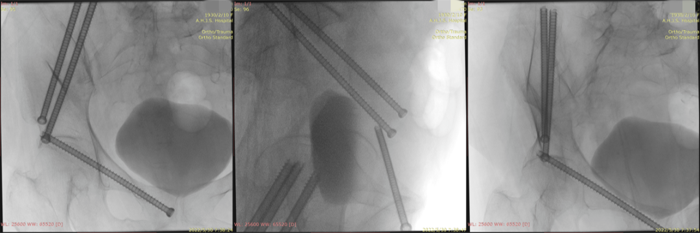

术中透视